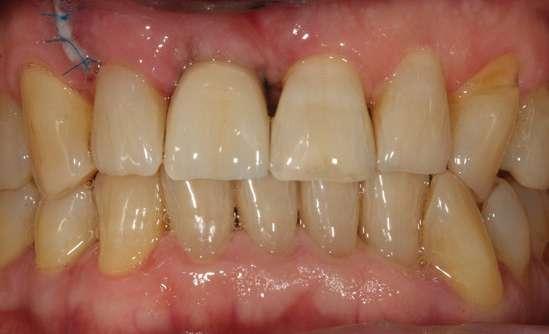

Presentamos el caso de un paciente masculino de 61 años de edad, bruxista, con evidentes desgastes en toda la dentición y cracks de esmalte que pueden observarse en las fotografías iniciales de la primera visita (figuras 1 y 2). En las fotografías

Figuras 1 y 2. Imágenes intraorales de la primera visita donde se hacen evidentes diferentes desgastes en los dientes anteriores y a mayor detalle crakcs en el esmalte, así como lesiones por abfracción en los cuellos de los dientes de los premolares y caninos superiores.

laterales se ponen de manifiesto aún más varias lesiones de esmalte que indican la parafunción en el paciente, unido a los desgastes excesivos en varias zonas (figuras 3 y 4). El paciente acude por dolor y movilidad en la pieza 11, que se ha incrementado en los últimos días, además de sensación de “diente crecido” que como podemos ver en las fotografías iniciales es real, ya que el diente se encuentra ligeramente extruido en relación con el contralateral. Estos signos parecen indicarnos una fractura o fisura. En la fotografía oclusal, podemos observar el desplazamiento del diente debido a la movilidad (figura 5). Posteriormente se realiza un sondaje positivo de la pieza, que lleva a 11 mm por lo que se confirma la sospecha de fractura y se procede a la exodoncia del diente, realizándose una regeneración posterior del alveolo con PRGF-Endoret y

Figuras 3 y 4. Fotografías laterales donde se evidencian los cracks de esmalte en varios dientes y los desgastes excesivos en varios puntos. En estas imágenes se hacen más evidentes las lesiones por abfracción.